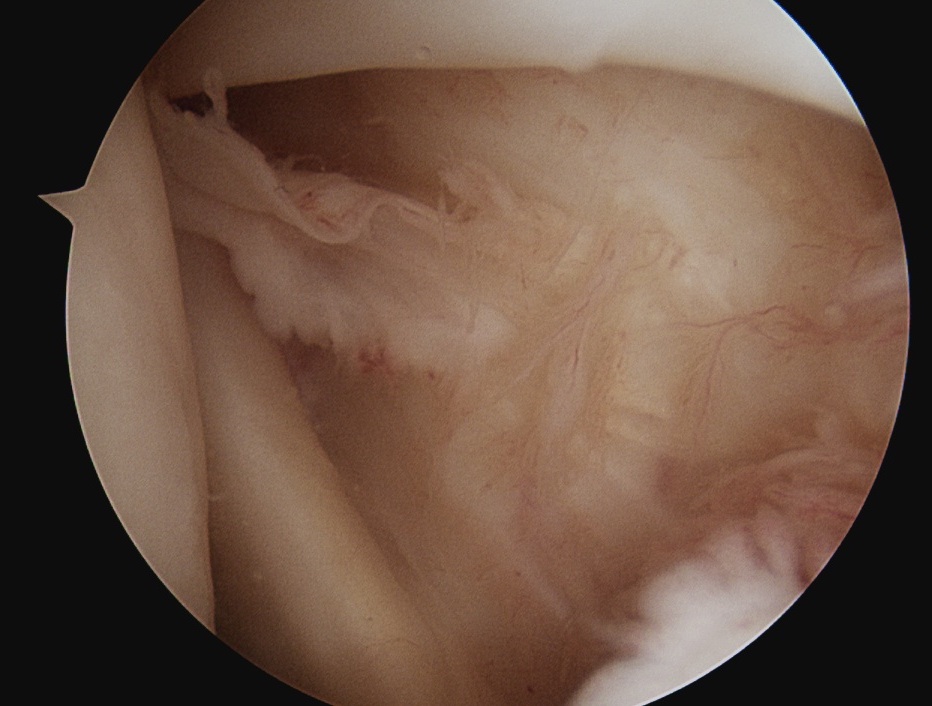

Shoulder arthroscopy

Rotator Interval - triangle of glenoid medial, biceps superior, subscapularis inferior

Humeral head cartilage

Glenoid cartilage

Labrum - anterior / inferior / posterior

Biceps tendon / insertion

Subscapularis

Glenohumeral ligaments

Three thickenings of the glenoid capsule: SGHL, MGHL, IGHL

| Superior glenohumeral ligament (SHGL) | Middle glenohumeral ligament (MGHL) |

|---|---|

|

Origin: Supraglenoid tubercle glenoid and coracoid Insertion: Proximal aspect medial edge lesser tuberosity of the humerus |

Origin: Distal aspect lesser tuberosity of humerus Insertion: Posterior aspect subscapularis |

Runs perpendicular to the middle GHL |

Crosses subscapularis vertically Variable size and shape in different people Cord like / leaf like / vestigal |

Stabilizes the long head of the biceps in its groove Limits external rotation of the humerus |

Limits external rotation with arm by side |

![]() |

| Inferior glenohumeral ligament (IGHL) | |

Origin: Inferior 2/3 glenoid and labrum Insertion: Anatomical neck humerus

Anterior band: antero-inferior glenoid to 3 o'clock Posterior band: postero-inferior glenoid to 9 o'clock Axillary pouch between two bands |

| Most important ligament in terms of stability | Stabilizes arm at 90 degrees of abduction |

Anterior IGHL glenoid attachment |

IGHL humeral attachment |

Inferior recess

Loose body in inferior recess

Undersurface supraspinatus - abduct arm

Infraspinatus / bare area / Hill Sachs